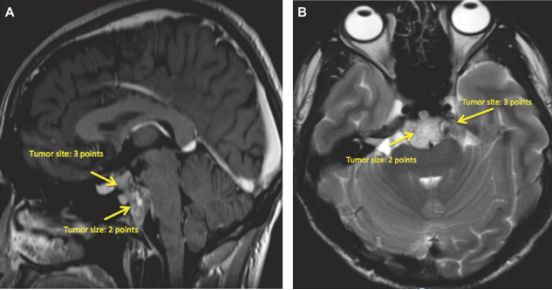

脊索瘤是罕见但具有挑战性的肿瘤,涉及颅底。术前分级系统将有助于确定治疗区域和风险因素,并与切除程度,并发症和复发相关。本文提出了新的颅脊索瘤分级系统。

新的分级系统包括肿瘤大小,肿瘤部位,血管包裹,硬膜内扩张,脑干侵犯,以及手术或放疗后肿瘤复发,得分为2至25分。在该研究中,采用新分级系统评估42例颅脊索瘤患者的风险,包括低风险(0至7分),中等风险(8至12分),高风险(≥13分),验证了新分级系统与切除手术次数,切除程度,并发症的数量和类型,复发和生存等均相关。

作者认为,新的脊索瘤分级系统可以帮助外科医生预测病例的难度,在术前掌握需要重点关注的颅底区域,以便于后续治疗方案的制定。